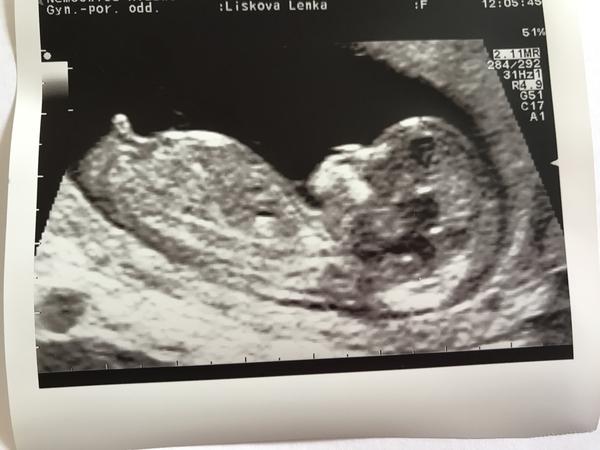

@llenka_li Moc gratuluji, UTZ krásný, je to úplně neuvěřitelné že tak brzy je to už takové miminko!